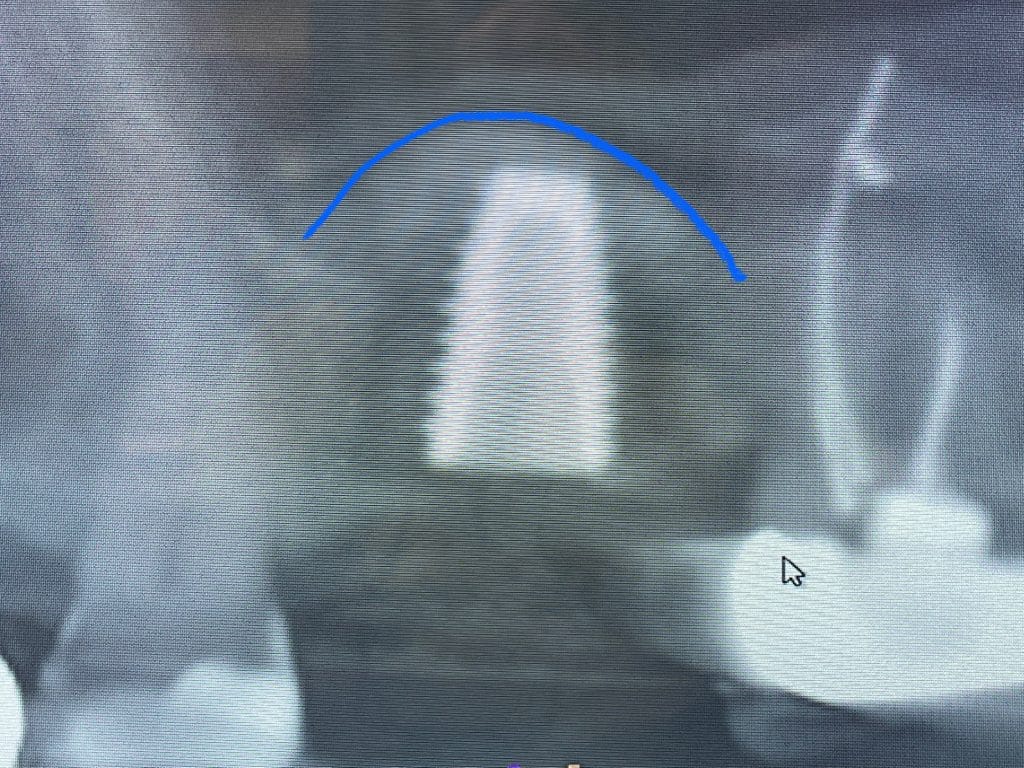

A sinus augmentation, or sinus lift, is a surgical procedure designed to increase bone volume in the upper jaw near the back teeth (molars and premolars) to support dental implants. It involves lifting the sinus membrane and placing bone graft material in the space between the jawbone and the sinus cavity. This procedure is often necessary when there is insufficient bone height or density in the area due to factors like bone loss from periodontal disease, tooth loss, or natural anatomy. Without enough bone, dental implants cannot securely anchor in place, which is crucial for their stability and longevity. A sinus augmentation provides the necessary foundation, enabling successful placement of implants and restoration of full oral function.

At Pioneer Valley Dental, sinus augmentations are commonly performed alongside implant surgery to ensure optimal results. Using advanced technology, we begin by taking 3D scans of the upper jaw to evaluate your anatomy and determine the best approach for the procedure. Digital impressions are then taken, and a custom surgical guide is 3D-printed to enhance precision. During the procedure, this guide assists your doctor in gently lifting the sinus membrane, adding bone graft material to increase bone volume, and securely placing the implant. This streamlined process ensures accuracy, safety, and successful outcomes for our patients.